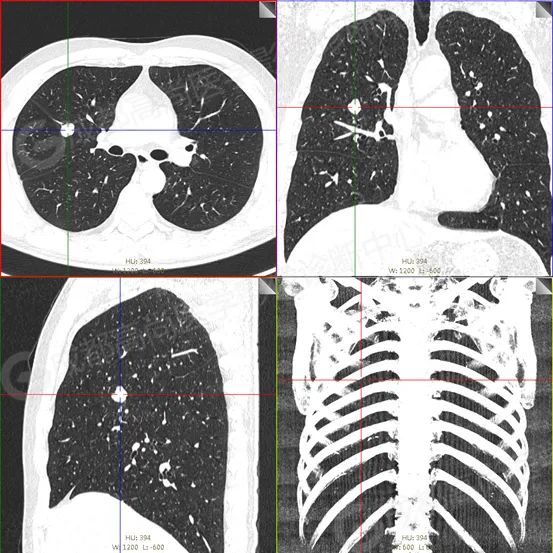

【HRCT】

右肺上叶前段及右肺中叶外侧段分叶状软组织结节,该病变骑跨水平裂胸膜,大小约 1.5 cm×1.3 cm×1.6 cm(上下径),边界清晰,其内密度欠均匀,CT 值约 18 Hu,FDG 摄取未见明显增高。

CT 表现类圆形结节或肿块,边界清晰,可有分叶,病灶内可见脂肪密度及钙化灶,爆米花样钙化为肺错构瘤的典型改变(约 10~15% 会出现),对肺错构瘤的定性诊断具有重要意义,但近一半病例无脂肪及钙化时,诊断困难。